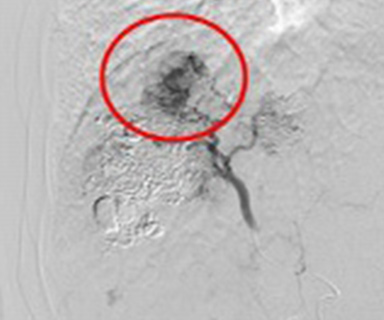

脳動静脈奇形

この検査では脳への血管が狭くなっているか、動脈瘤(血管のコブ)があるか、脳出血や脳腫瘍などの周辺に重要な血管があるか、異常な血管があるかなどを調べます。

またクモ膜下出血の原因となる脳動脈瘤や動脈や静脈の異常血管(脳動静脈奇形など)をプラチナ製の針金(コイル)を詰め、血流を遮断して治療することができます。